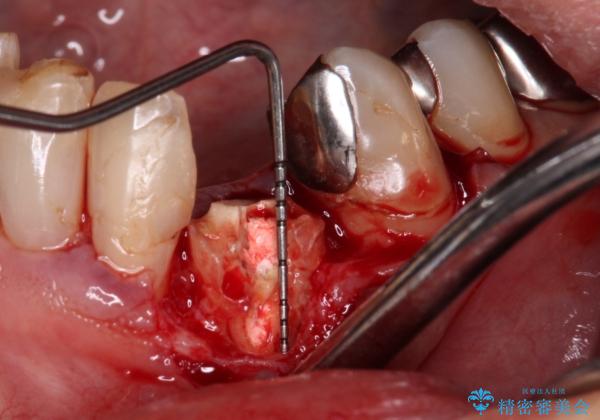

麻酔下で歯肉を開いて診察をしたところ、唇側の歯肉縁下に深く歯が欠けている状態でした。

当該歯である犬歯は歯根が長く、安易に抜歯することはおすすめできないため、まずは部分矯正により歯根を引っ張り出し、その後歯周外科処置により歯槽骨や歯肉の状態を整え、最終的にはオールセラミッククラウンにて補綴治療を行うこととしました。